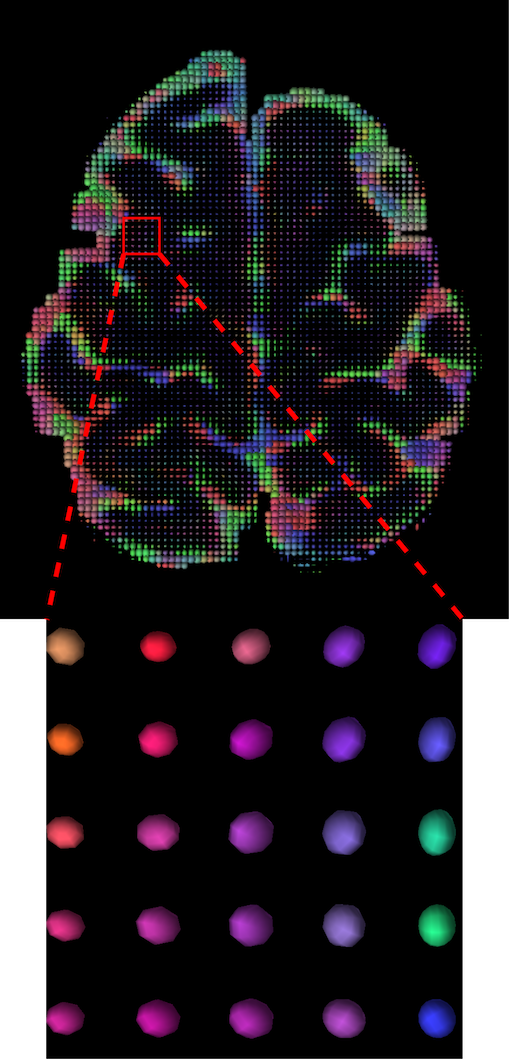

The visualization of inpainted results (showing the whole diffusion tensor for each voxel) generated from different models are demonstrated in Figure 3, where the tensor is represented in RGB coding that colours red, green and blue represent diffusion in the x, y, and z axes respectively. One typical example of reconstruction in the disrupted ROIs has been zoomed for visualization. Compared to the ground truth, TW-BAG is able to generate more distinct orientations following the original distribution and intensity across sagittal, coronal and axial views, which could demonstrate water diffusivity (denoted by eigenvalues of tensor model) more accurately. As indicated in Figure 4, the boundaries and textures of the FA map for TW-BAG are less blurry than the other competing models, validating the effectiveness of TW-BAG from a neuroscience perspective.